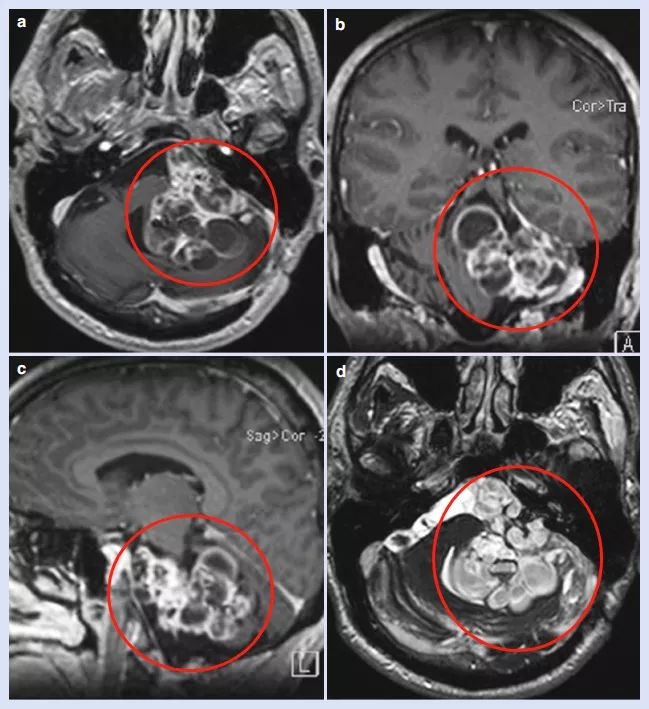

术前MRI图像,脑干小脑角区较大肿瘤占位,严重压迫脑干

事实证明他的决定明智,因为德国汉诺威国际神经外科研究所(INI)神经外科教授在详细研究了他的病历资料后,表示可以为他完成这台高难度手术。因Adam的病情已经严重,考虑到肿瘤较大、已对脑干和下颅神经造成严重的压迫与损伤,为了术中的生命顺利,在手术前为他做了气管切开术。

尽管肿瘤与周围组织严重粘连、正常组织结构损害、蛛网膜平面缺失,医生仍通过标准的乙状窦后入路(RS)为Adam顺利全切了较大的听神经瘤,但术中却无法识别面神经、面神经损伤严重,因其早已在以往的手术中被损害了,如果一次手术就能在确定患者顺利和神经功能保护的前提下全切肿瘤,肿瘤很可能不会这样频繁地复发,面、听神经可以得到较好保存,避免脑干及多种颅神经损伤的并发症,患者的生活质量也不会被牺牲至此。